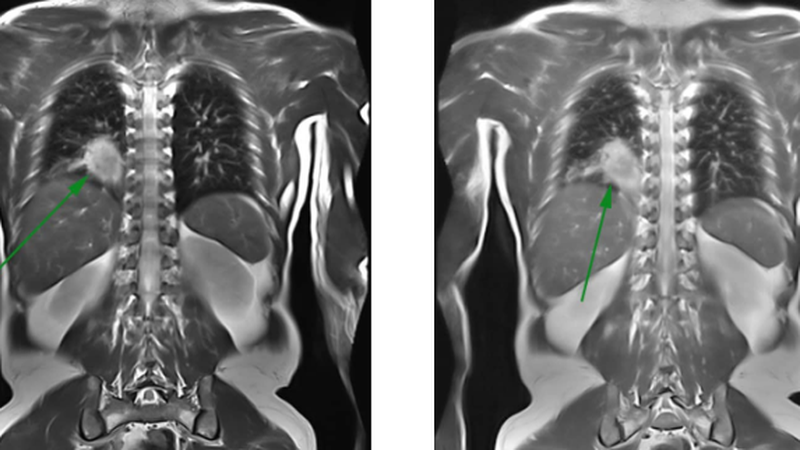

Chụp MRI phổi có vai trò gì? Cần lưu ý điều gì trước khi chụp MRI phổi? 2 Chụp MRI đánh giá được những tổn thương ở lồng ngực

Do đó, phương pháp chụp cộng hưởng từ MRI ra đời đã giải quyết được phần nào vấn đề này. Đặc biệt, MRI có vai trò quan trọng trong đánh giá tổn thương lồng ngực, thành ngực và khoang màng phổi, tại tim, phổi. Chụp cộng hưởng từ MRI có hình ảnh đa diện, độ tương phản cao trong đánh giá tổn thương mô mềm, không bức xạ ion ảnh hưởng đến đánh giá mạch máu. Đặc biệt, phải kể đến độ nhạy cao của chụp MRI trong đánh giá các tổn thương thành ngực nguyên phát, nhiễm trùng và xâm lấn, bao gồm:

• Đánh giá tổn thương nhu mô phổi: Mặc dù còn nhiều hạn chế trong đánh giá này, tuy nhiên chụp MRI vẫn phân biệt được tổn thương trong bệnh tổ chức kẽ và ác hay lành tính.

Với những ưu điểm trên, chụp cộng hưởng từ MRI có thể giúp bác sĩ và bệnh nhân mắc ung thư phổi hay gặp phải các bệnh lý về phổi liên quan phát hiện sớm ra bệnh, từ đó có phương pháp điều trị phù hợp. Hiện nay, phương pháp chụp MRI hiện đại này ngày càng được áp dụng phổ biến trong sàng lọc và chẩn đoán sớm bệnh lý phổi.